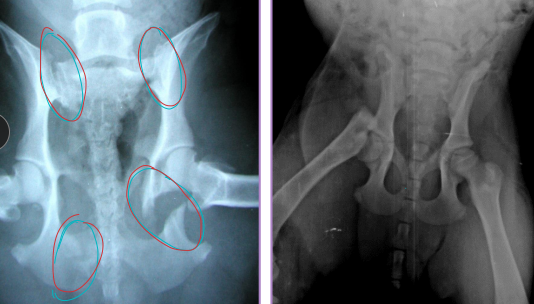

Pelvis Fractures

Considerations: Multi physes, normally breaks at multi sites

Sciatic n.: through ischiatic notch

Weight transfer: paw → tibia → femur → acetabulum → ilium → SI joint

Et: males > females, trama

Dt: Rads, CT for complex fractures/Sx planning

Tx:

Rx: non-displaced, unilateral, non-articular, non-weight-bearing fractures

6 w crate rest, sling, pain control, controlled walks, PT

Sx: ilium/acetabulum/SI joint (weight-bearing), bilateral fractures, displacement, colon compromise, pelvic canal compromise (parturition), sciatic entrapment

Ilium: plate + screws

Acetabulum: plate + screws, cross pins, PMMA

SI joint: screw stabilization